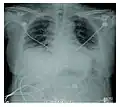

Radiographie montrant une réduction marquée de la capacité pulmonaire_Idiopathic_DAD_3.jpg)

La progression rapide des symptômes initiaux à l'insuffisance respiratoire est une caractéristique clé. Le diagnostic s'appuie sur une tomodensitométrie (TDM) permettant d'écarter les autres causes de lésion aigüe du poumon[3]. Une biopsie du poumon qui montre l'organisation de lésions alvéolaires diffuses peut aussi être pratiquée. D'autres tests de diagnostic sont utiles pour exclure d'autres conditions similaires, mais l'histoire, la radiographie et la biopsie sont essentielles. Ces autres tests peuvent inclure des analyses sanguines de base, des hémocultures et un lavage bronchoalvéolaire.